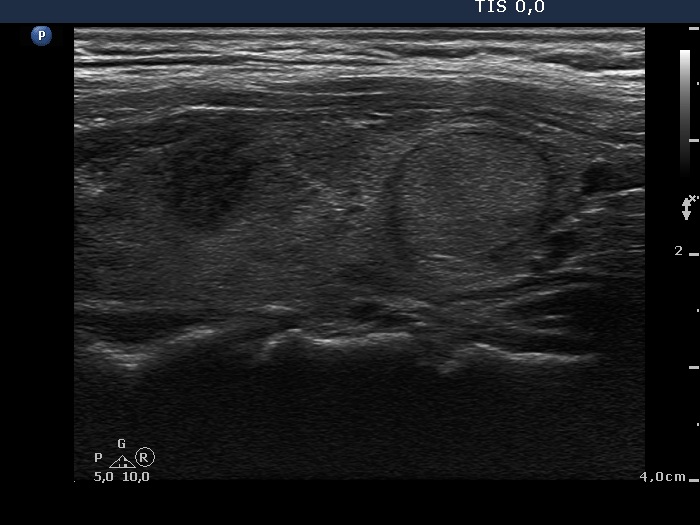

Discrete lesion or nodule in Hashimoto's thyroiditis - case 10 (95) (ultrasonographic picture 7)

Left lobe, another longitudinal view.